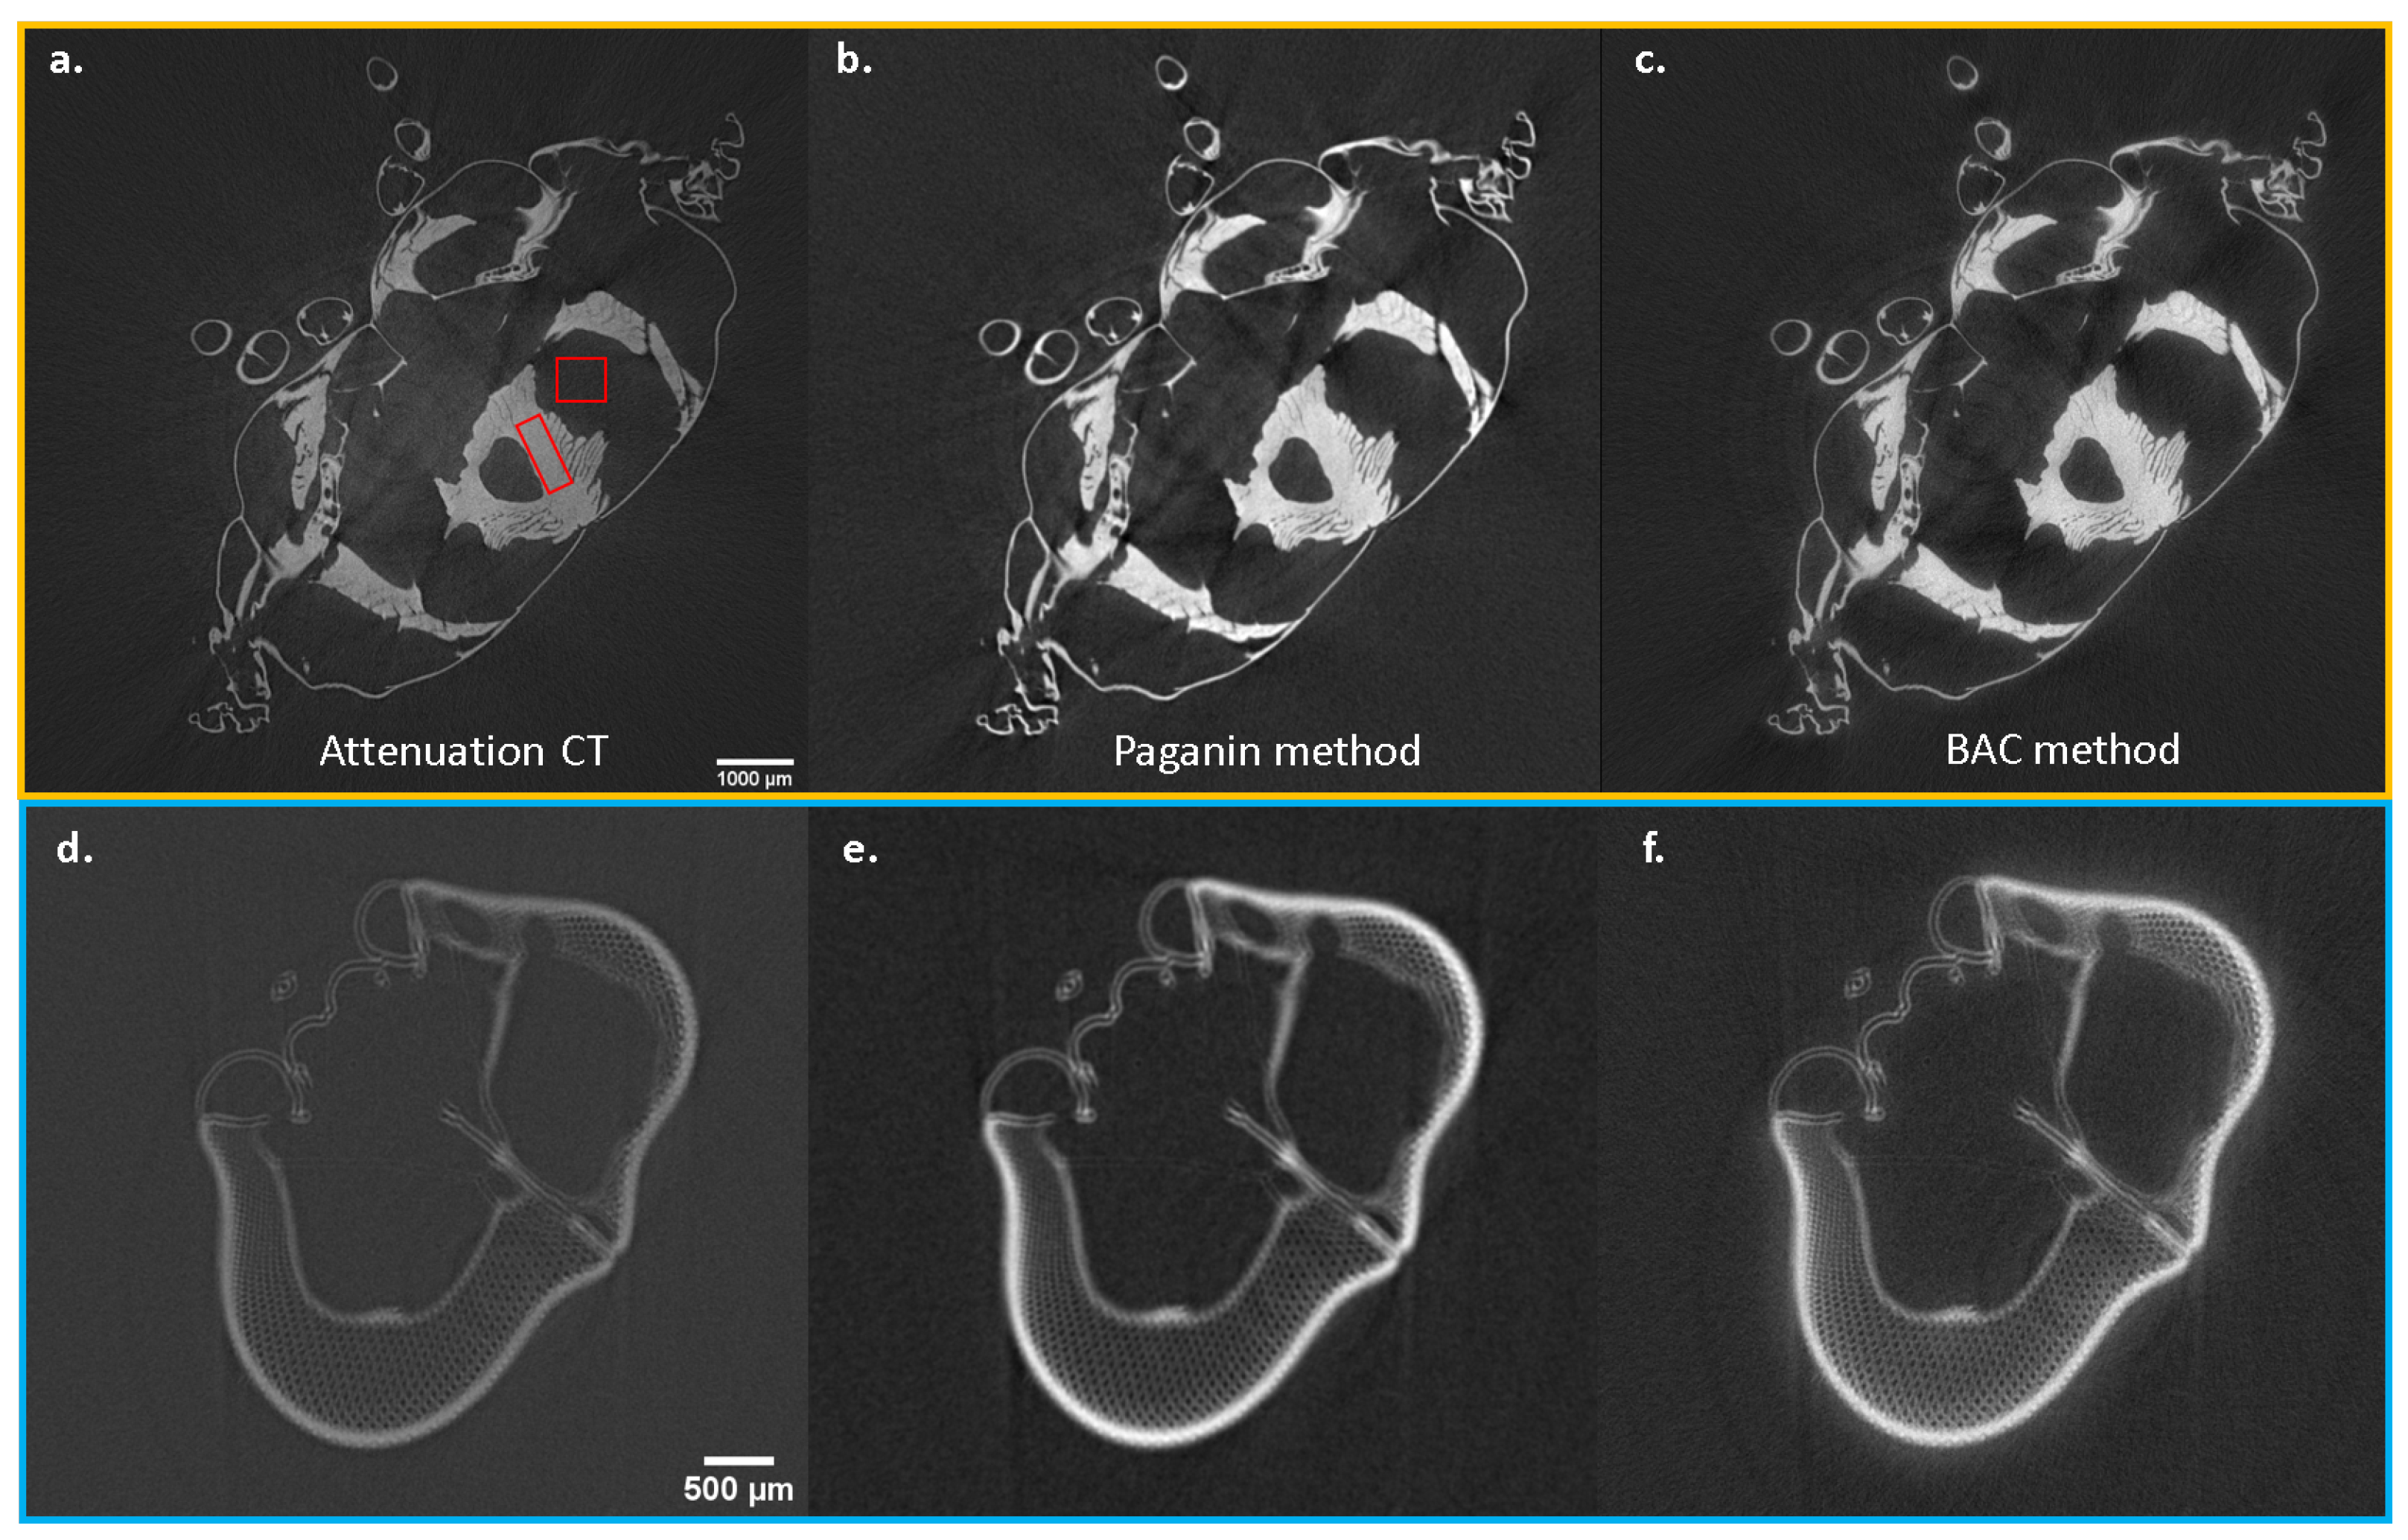

3.1. Example for the Paganin Method

3.2. Example BAC Method

3.3. Example for Grating-Based PCI